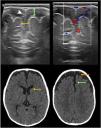

Macrocephaly is a clinical term defined as an occipitofrontal circumference more than two standard deviations above the mean. It is present in 5% of children and is a common indication for imaging studies. There are multiple causes of macrocephaly; most of them are benign. Nevertheless, in some cases, macrocephaly is the clinical manifestation of a condition that requires timely medical and/or surgical treatment. The importance of imaging studies lies in identifying the patients who would benefit from treatment. Children with macrocephaly associated with neurologic alterations, neurocutaneous stigmata, delayed development, or rapid increase of the circumference have a greater risk of having disease. By contrast, parental macrocephaly is predictive of a benign condition. Limiting imaging studies to patients with increased risk makes it possible to optimize resources and reduce unnecessary exposure to tests.